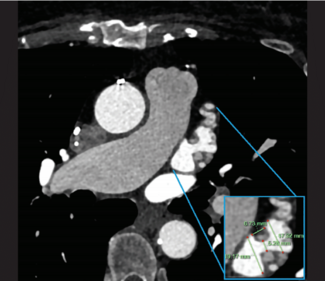

Alok Gambhir, MD, PhD, FACC, FHRS; John Ricketts, MD, FACC

Alok Gambhir, MD, PhD, FACC, FHRS, and John Ricketts, MD, FACC, present a case of transcatheter left atrial appendage (LAA) closure in a patient who had incomplete surgical closure of the LAA.